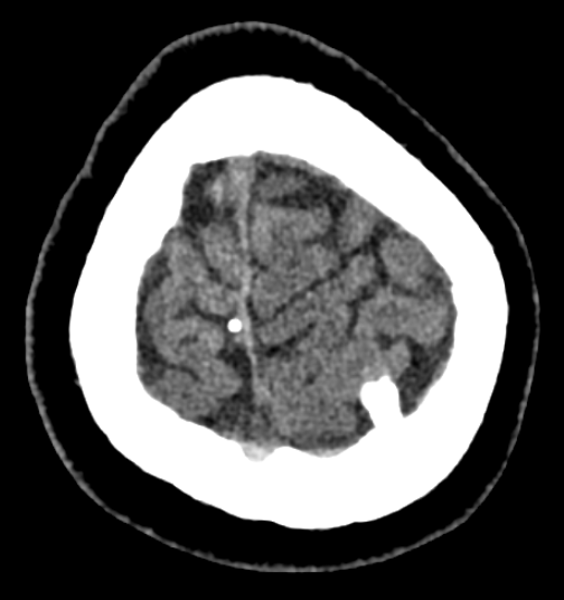

入院后,医院为她进行了详尽的颅脑MRI增强及头颅CT薄扫检查,结果显示其病变位于左侧顶上小叶,病变对脑组织压迫明显(病变周围脑组织CBF灌注明显降低、较对侧脑回体积明显减小),且与左侧大脑上静脉紧密相关,动态视频脑电图分析进一步提示病灶周围脑组织存在异常放电。

术前CT图像